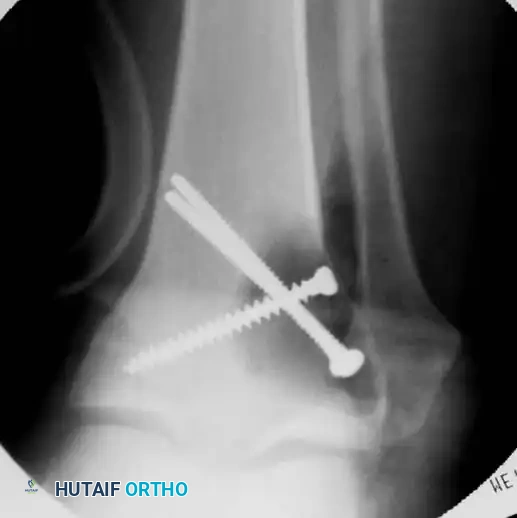

Following extended curettage, the structural integrity of the bone is compromised. The defect is typically reconstructed using PMMA cement, often augmented with internal fixation (screws or plates) to prevent pathological fracture.

Intraoperative view of a curetted cavity packed with PMMA cement and augmented with structural screws.

Postoperative radiographs demonstrating successful extended curettage, cementation, and screw augmentation of a distal tibial lesion.